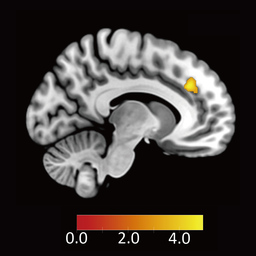

そこで、分配の受入れ/拒否という行動選択と反応時間の両方から意思決定を分析できる「ドリフト拡散モデル(Drift Diffusion Model:DDM)」を用いて解析を行いました。具体的には、「不公平な提案に対する不快な感情を抑えることで提案を受け入れる」という過程に関わる脳部位を明らかにするため、DDM解析を用いて、不公平な提案をより受け入れる参加者ほど、不公平に対して強く反応する脳領域を探索しました。その結果、背側前帯状皮質が見つかりました(図3A参照)。

図3(A)不公平な提案を受け入れる参加者ほど不公平に対して反応する脳領域(背側前帯状皮質)